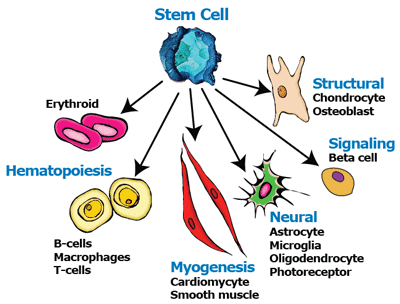

什么是干细胞?

干细胞是指没有分化为特定细胞类型的细胞, 这些特定类型的细胞组成人体特定的组织和器官,如神经、血液、软骨等。干细胞具有自我复制和分化为多种人体细胞的能力。干细胞分为受精卵来源的胚胎干细胞和成体干细胞,成体干细胞存在于各种人体组织中。

干细胞是指没有分化为特定细胞类型的细胞, 这些特定类型的细胞组成人体特定的组织和器官,如神经、血液、软骨等。干细胞具有自我复制和分化为多种人体细胞的能力。干细胞分为受精卵来源的胚胎干细胞和成体干细胞,成体干细胞存在于各种人体组织中。

当胚胎干细胞移植入患者体内后会引起肿瘤或免疫反应。相反,成体干细胞也就是间充质干细胞的免疫调节功能使其在人和动物体内可以避免异种移植排斥反应的发生。另外,间充质干细胞在临床试验中没有出现不良反应,因此,间充质干细胞在治疗疑难杂症和组织再生方面具有远大前景。

间充质干细胞具有多向分化性、归巢效应以及旁分泌作用,是组织修复中最有潜力的干细胞。CARTISTEM的活性成分为脐血间充质干细胞,间充质干细胞(MSC)具有分化为骨骼、软骨、肌肉、骨髓基质、脂肪的能力。脐血间充质干细胞在损伤软骨微环境中损伤因子的刺激下,还可以分泌生长因子、细胞因子以及配体等复杂基质。